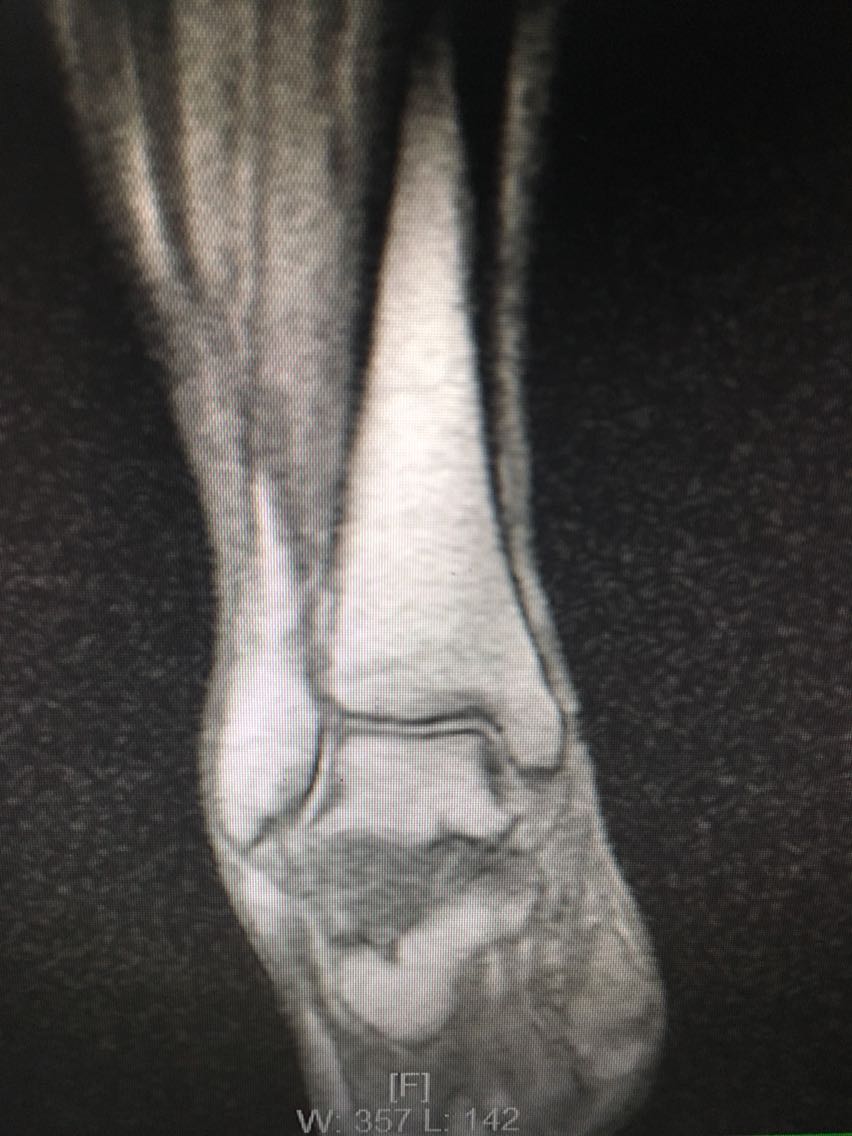

主诉:反复右侧踝关节扭伤3年余。 病史:患者F/60,自述3年前扭伤右足踝,未予以重视及治疗,后反复出现右侧踝关节扭伤,目前自觉右踝松弛,不能做剧烈运动,局部无明显疼痛。

查体:右踝关节踝前抽屉试验和内翻试验阳性,局部无压痛。 辅查:MRI检查如下